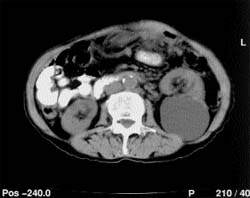

Патология живота: снимки компьютерной томографии с ишемическим энтеритом